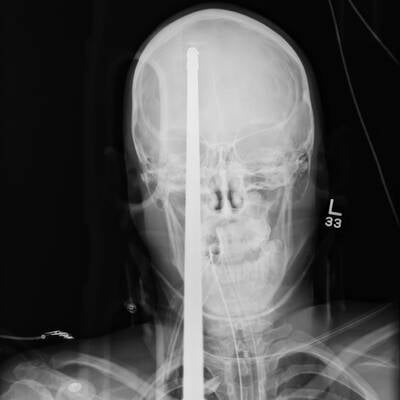

Es ist ein Wunder: Eine zwei Meter lange Eisenstange durchbohrte den Kopf von Eduardo Leite (24) aus Brasilien – und der Bauarbeiter hat es überlebt!

Ein wahres Wunder hat sich in Rio de Janeiro (Brasilien) ereignet: Eine Eisenstange stürzte aus gut 5 Metern Höhe auf den 24-jährigen Bauarbeiter Eduardo Leite. Ein Aufschrei bei seinen Kollegen, als sich die Stange durch seinen Helm hindurch in den Kopf bohrt und zwischen den Augen wieder heraustritt – ein Bild des Horrors!

In einer Notoperation kämpften die Ärzte um das Leben von Eduardo Leite. Sie öffneten den Schädel und entschieden sich, die Stange aus der gleichen Richtung zu entfernen, aus der sie in den Kopf eingedrungen war.